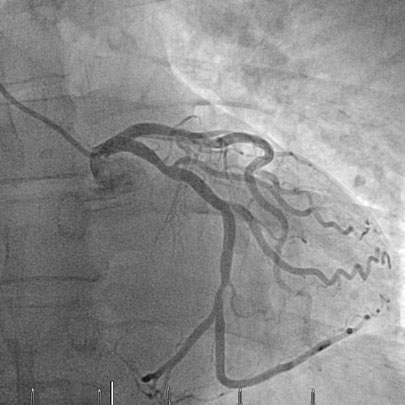

A total of 85/200 patients (42.5%) exhibited incidental findings requiring immediate further medical workup and/or treatment. Of note, most incidental findings here were newly diagnosed cardiovascular conditions, with coronary artery calcification being the most prevalent finding followed by arterial aneurysms and incidentally detected embolism (table 2, figs 1, 2a and 2b ). Pancreatic and liver tumours were less frequent, but significant. Examples of incidentally diagnosed tumours are shown in figures 3 and 4 .

Figure 2a Intra-arterial coronary angiogram showing a high-grade stenosis of the circumflex branch of the left coronary artery prior to drug eluting stent placement.

Figure 2b Intra-arterial coronary angiogram after drug eluting stent placement.